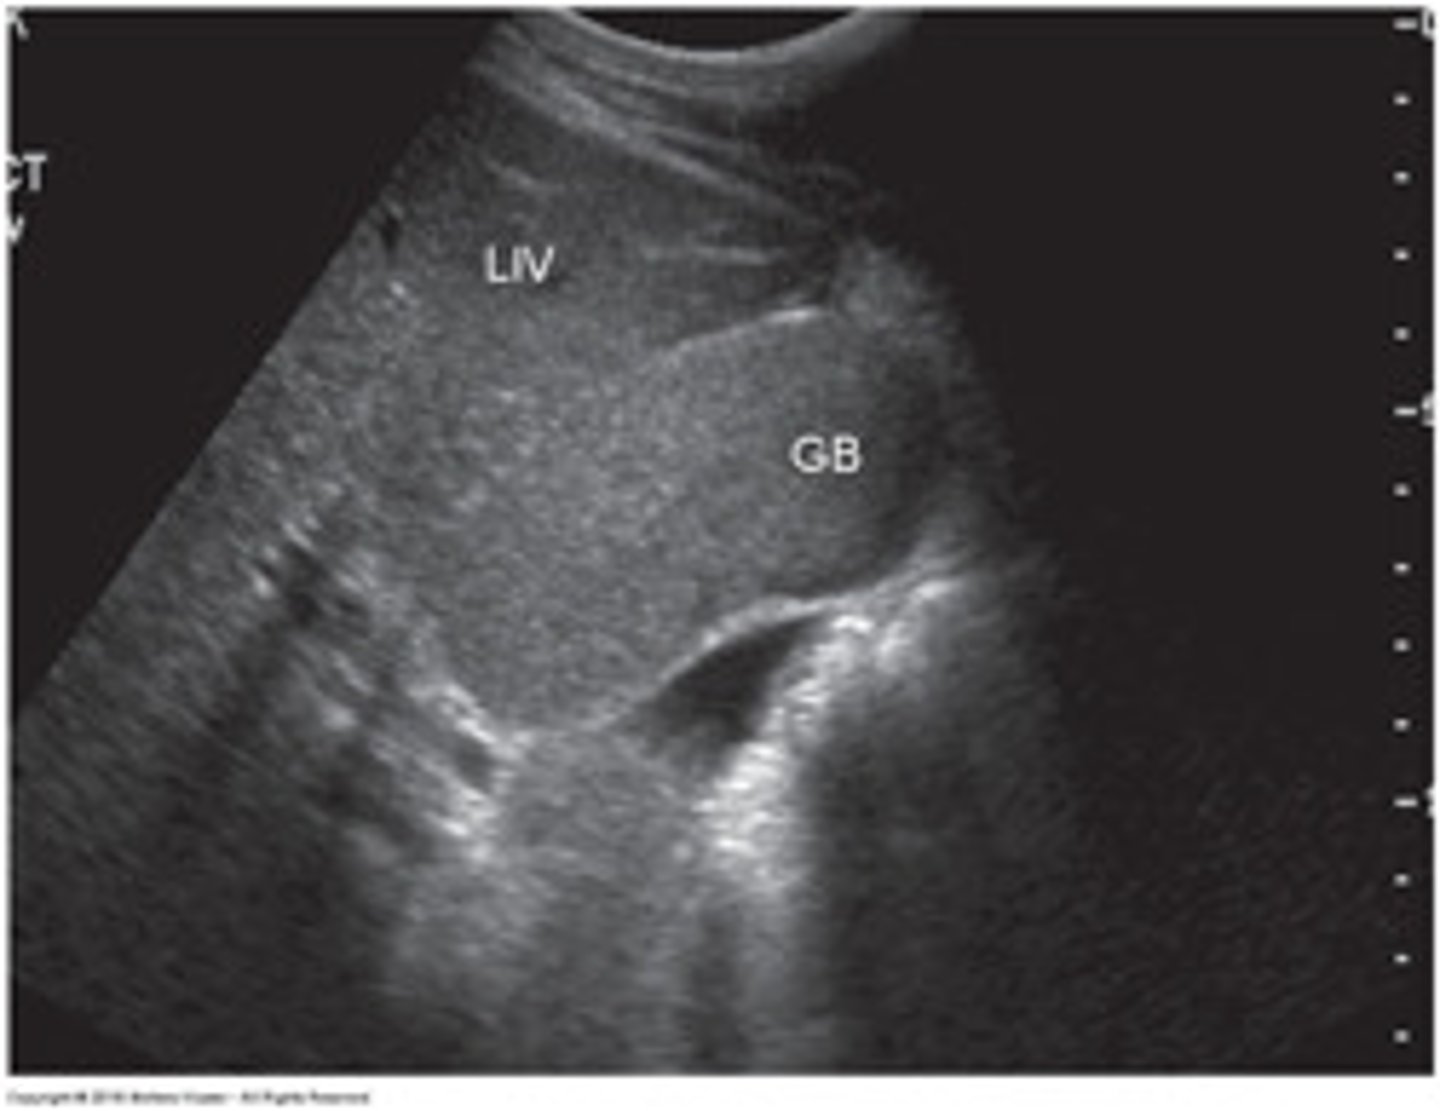

In the sagittal plane, the GB appears as an:

anechoic, pear-shaped structure located anterior to the right kidney and lateral to the head of the pancreas and duodenum

landmarks for identifying GB

Interlobar fissure/Main Lobar Fissure - appears as echogenic

linear structure connecting GB to MPV.